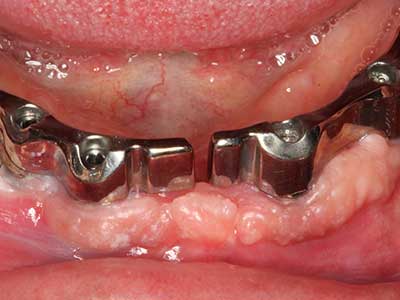

Marginal periodontal diseases are the main reason for extractions in advanced age. These diseases are primarily caused by bacterial colonization of the gingival pocket, which causes inflammation followed by loss of the periodontium. The formation of subgingival biofilms and concrements is a significant aetiological factor for marginal bone atrophy, so their removal is an important part of the treatment (Drisko 2014, Plessas 2014).

Initial and surgical treatment phases are differentiated in the treatment of marginal periodontitis. In addition to instruction in oral hygiene and motivating patients, both phases should include adequate cleaning of the root surface. In the regenerative setting an open access is generally preferred. The root surface can be cleaned by piezo surgery using special attachments, where instruments with different curvatures are used to reach areas that are difficult to access, such as furcations. The integrated irrigation in the system flushes the detached concrements and bacteria out of the pocket. Specialized systems such as the Piezomed also include application feedback to minimize the ablation of hard dental substance. The greater the pressure on the periodontal attachment the greater the reduction in the amount of ablation.